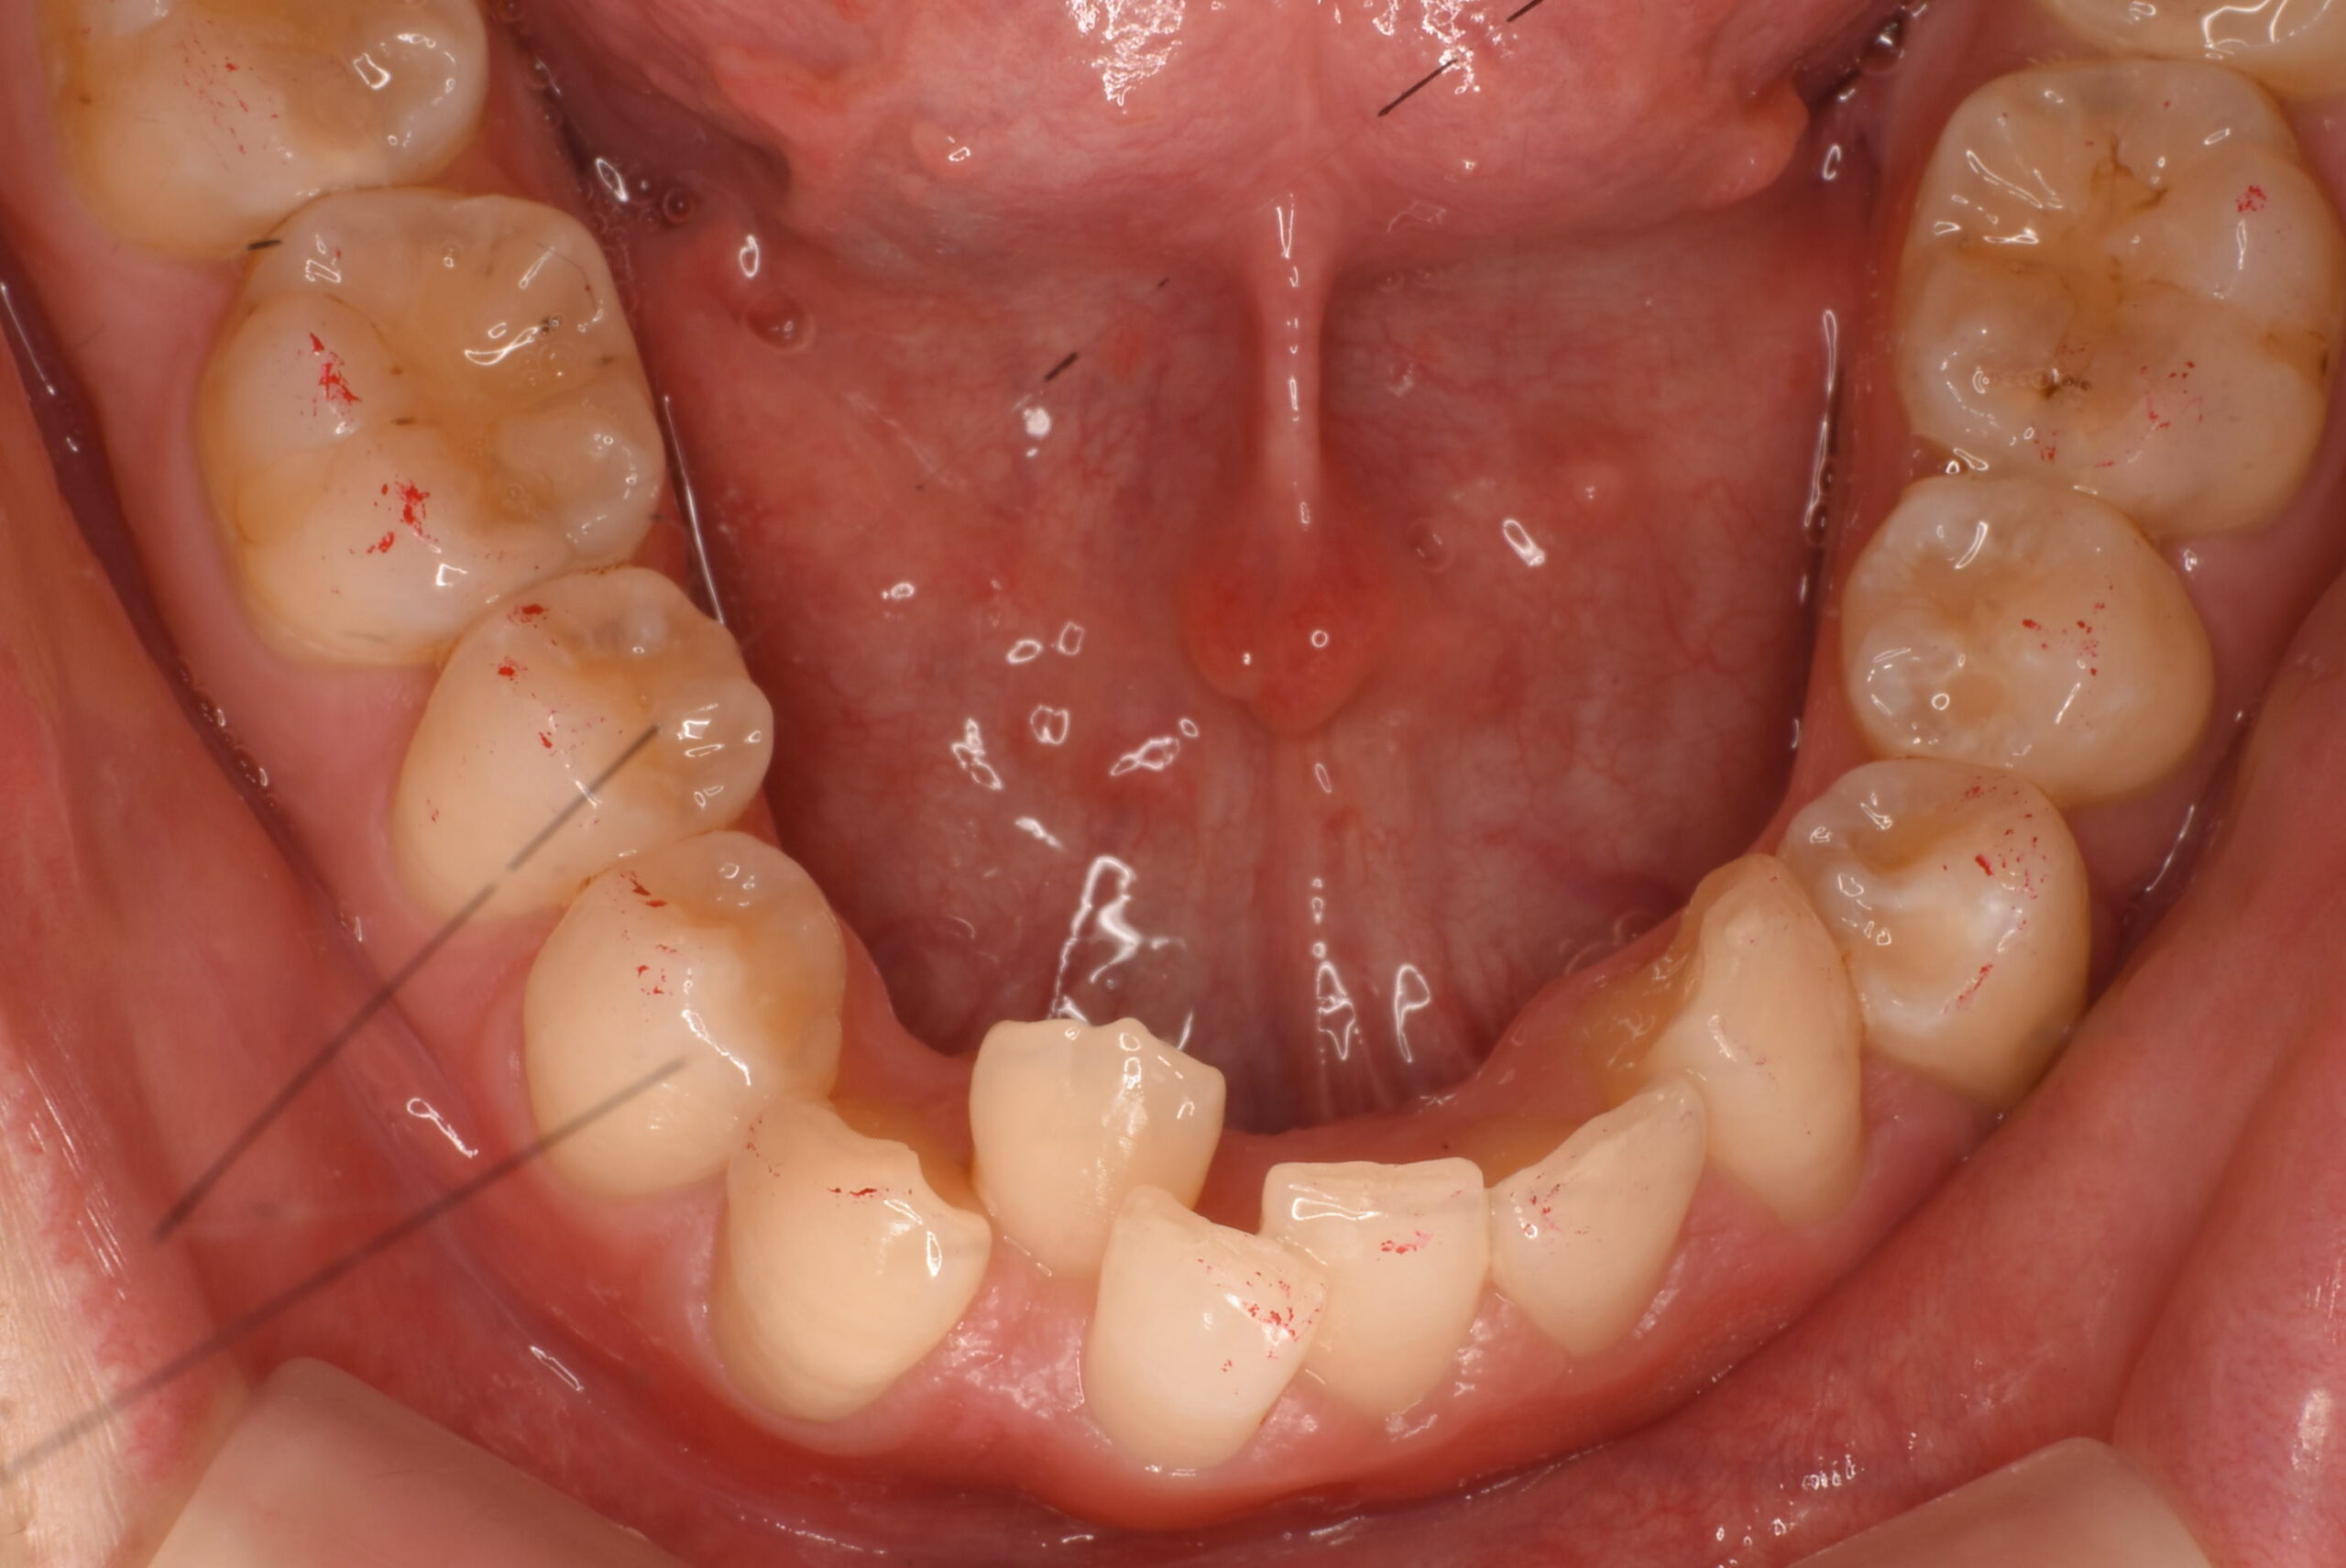

- BEFORE

治療前_下顎咬合面